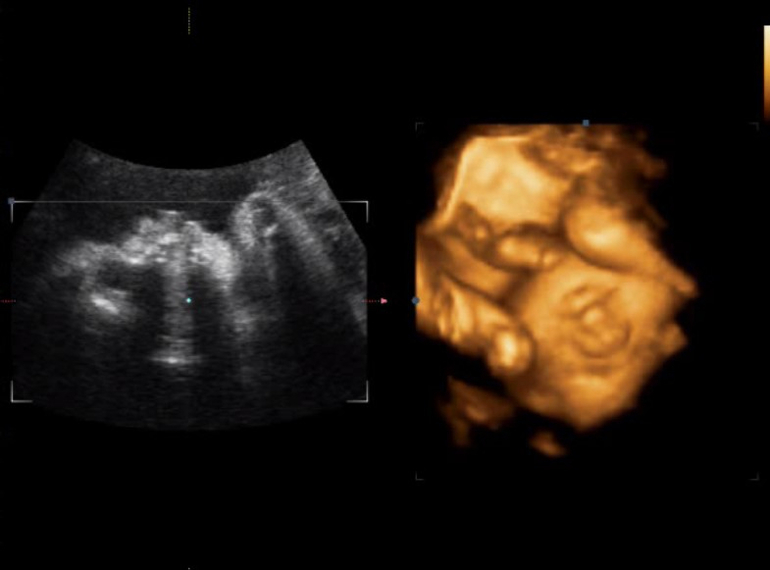

А это наши первые "фоточки", наверное, только счастливая мама может разглядеть здесь свои черты)))